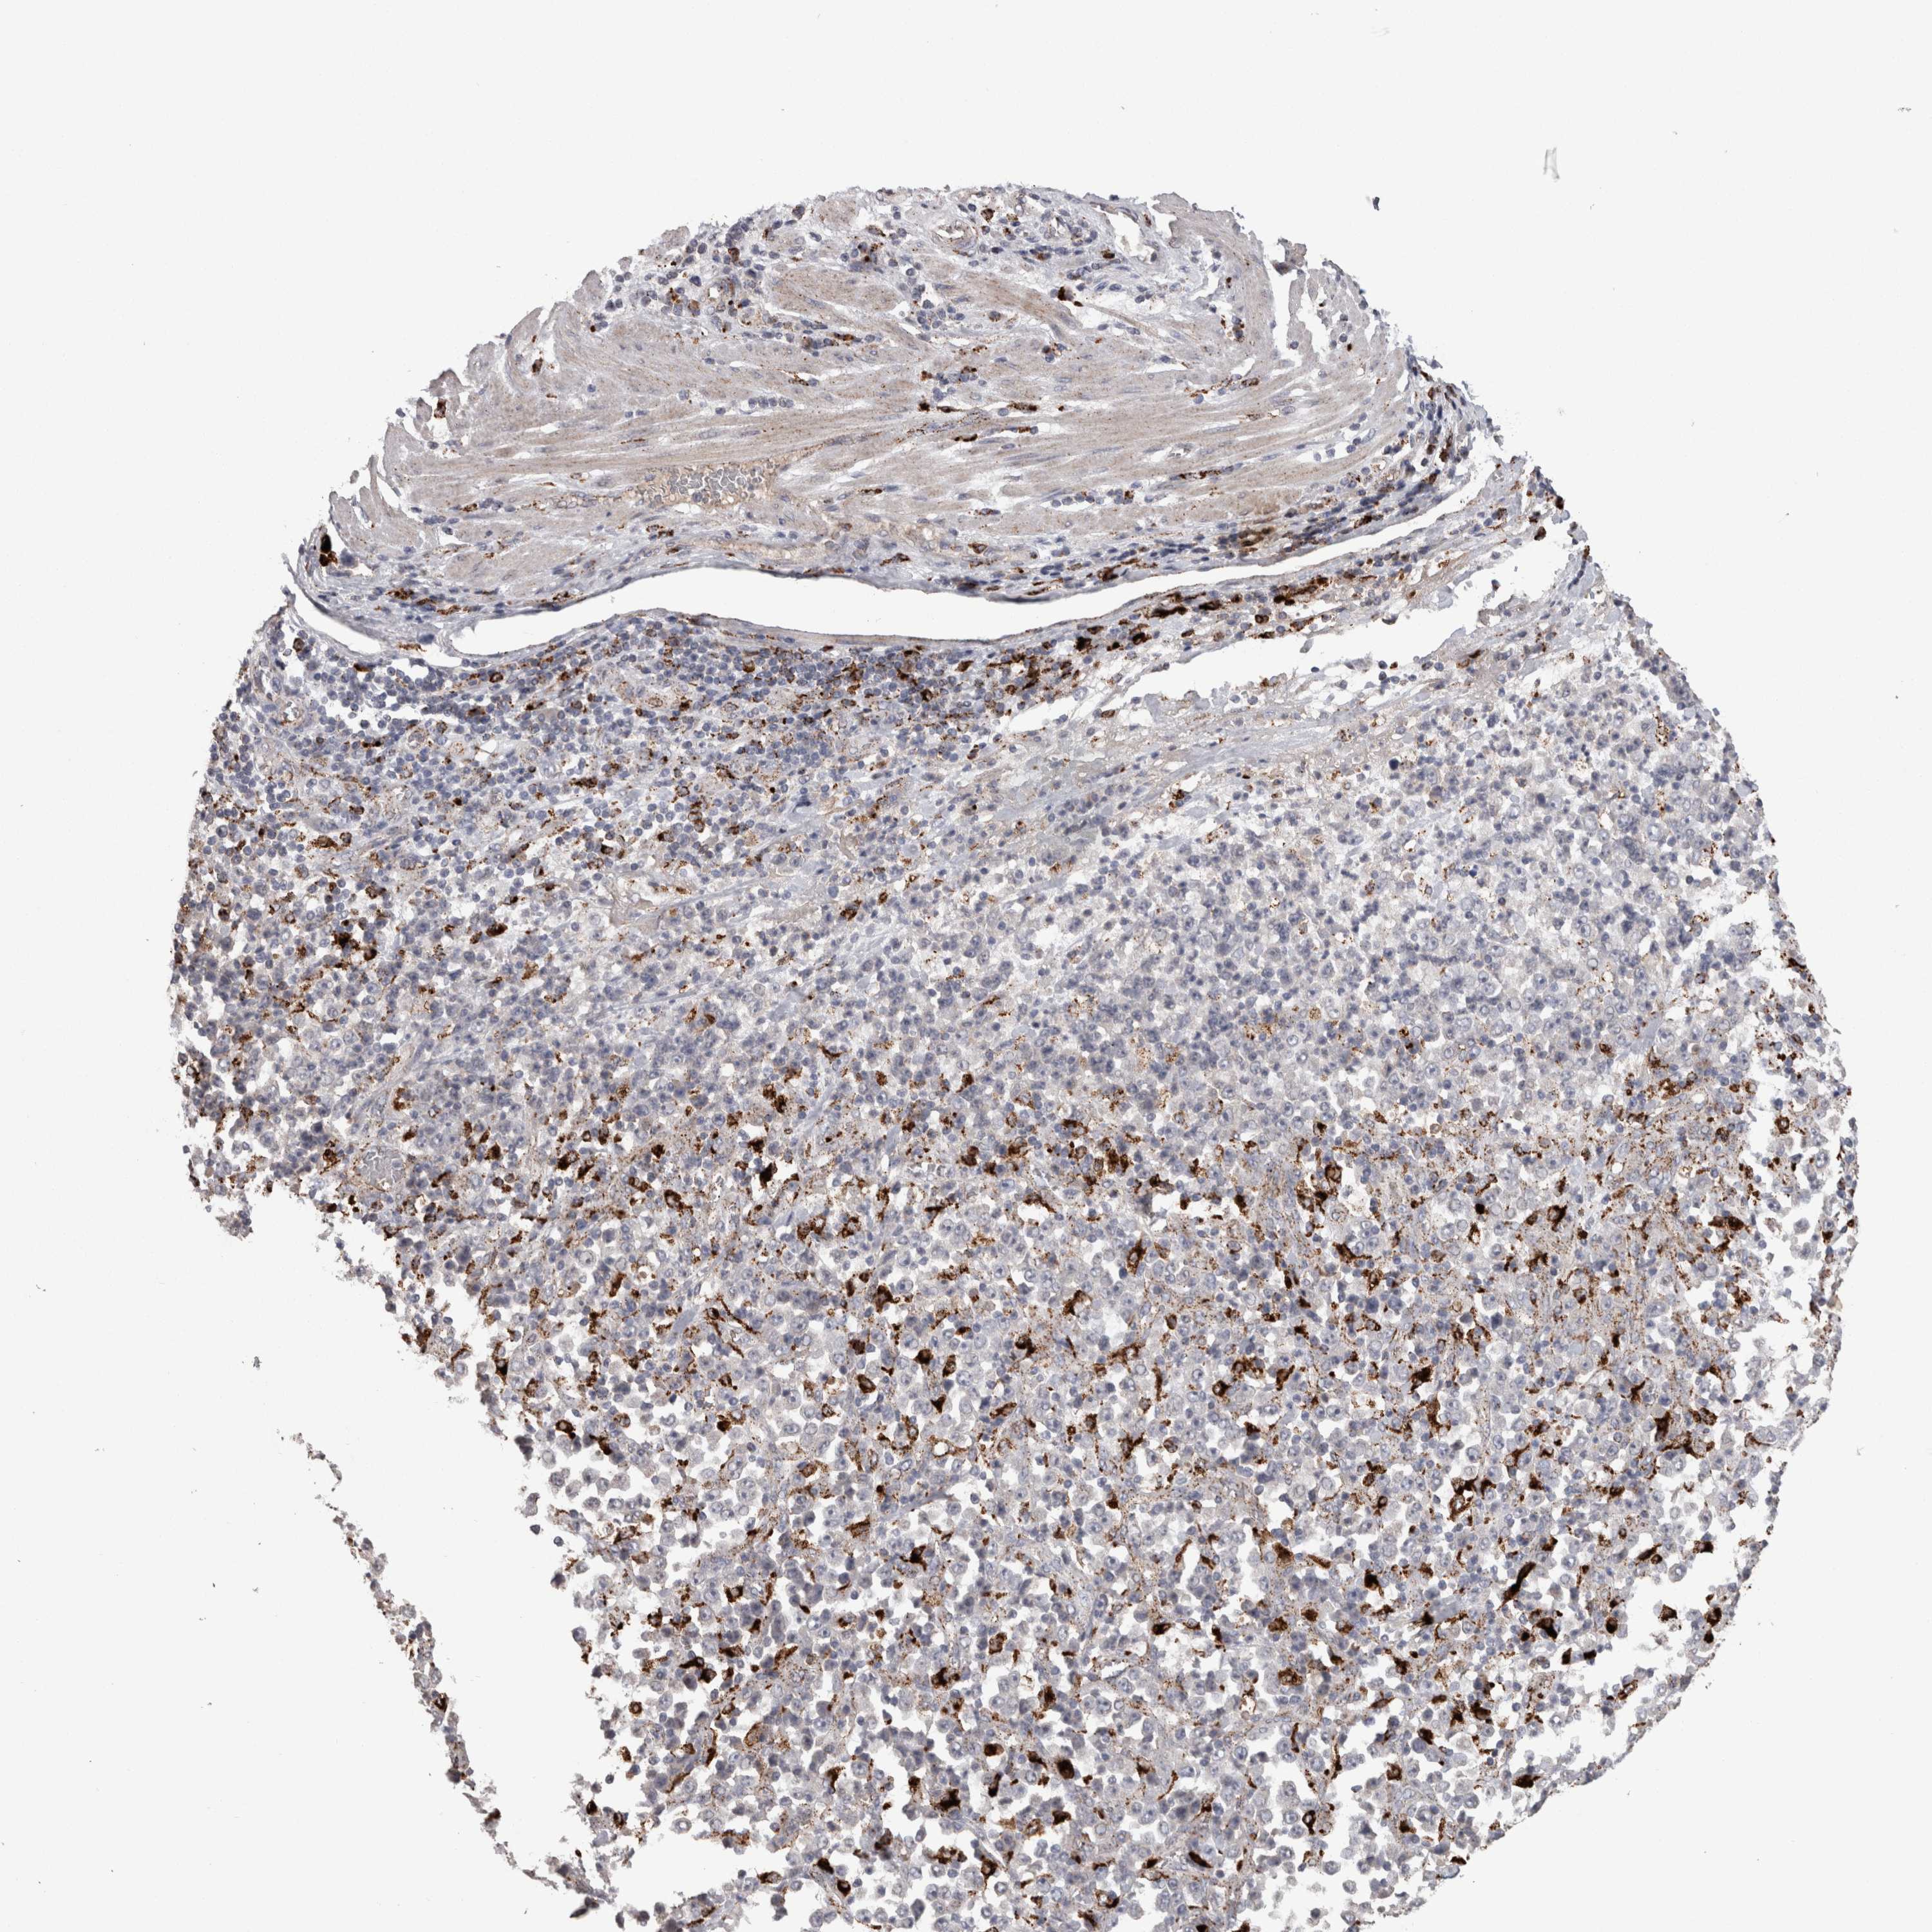

STOMACH CANCER - Protein expressioni

A mouse-over function shows sample information and annotation data. Click on an image to view it in a full screen mode. Samples can be filtered based on level of antibody staining by selecting one or several of the following categories: high, medium, low and not detected. The assay and annotation is described here.

Note that samples used for immunohistochemistry by the Human Protein Atlas do not correspond to samples in the TCGA dataset.

Antibody stainingi

Antibody staining in the annotated cell types in the current human tissue is reported as not detected, low, medium, or high, based on conventional immunohistochemistry profiling in selected tissues. This score is based on the combination of the staining intensity and fraction of stained cells.

Each image is clickable and will lead to virtual microscopy that enables deeper exploration of all samples and also displays staining intensity scores, fraction scores and subcellular localization as well as patient and tissue information for each sample.

Antibody HPA049876

Antibody HPA053504

Antibody CAB025114

Staining

High

Medium

Low

Not detected

Intensity

Strong

Moderate

Weak

Negative

Quantity

>75%

75%-25%

<25%

None

Location

Nuclear

Cytoplasmic/membranous

Cytoplasmic/membranous,nuclear

Adenocarcinoma, NOS